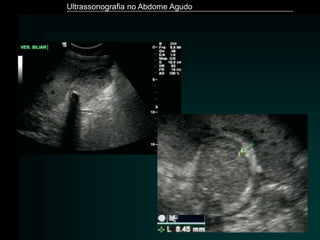

Colecistite Aguda

– US é o método de imagem de escolha

» Sensibilidade: 80 - 100%

» Especificidade: 60 - 100%

– Achados Ecográficos

» Presença de colelitíase

» VB distendida (diâmetro transverso > 4 cm)

» Espessamento da parede da vesícula (>3 mm)

» Aspecto lamelar da parede

» Perda de definição da parede

» Sinal de “Murphy Ultrassonográfico”

Ultrassonografia no Abdome Agudo

– Paciente com suspeita clínica de colecistite aguda *

» Apenas litíase vesicular

» Valor Preditivo Positivo: 88%

» Litíase vesicular + “Murphy US”

» Valor Preditivo Positivo : 92%

» Litíase + “Murphy US” + Espessamento parietal

» Valor Preditivo Positivo : 94%

* Ralls et al. Radiology.1985, 155:767–771

– Outros achados

» O cálculo pode não ser visibilizado

» Imagens hiperecogênicas com reverberação acústica

• colecistite enfisematosa

• bactérias produtoras de gás

» Conteúdo espesso / debris

• empiema

» Coleção pericística

• perfuração